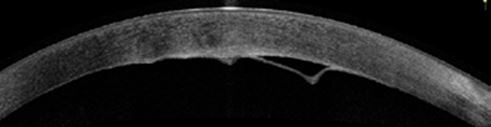

Η bullous ΑΔΜ χαρακτηρίζεται από ομαλή διόγκωση της Δεσκεμετείου στον πρόσθιο θάλαμο χωρίς την παρουσία ρήγματος και συνήθως προκύπτει από εσφαλμένη έγχυση BSS, ιξωδοελαστικού ή αέρα στον υπερδεσκεμέτειο χώρο μέσω των χειρουργικών τομών. Σπανίως, μπορεί να προκληθεί από την ενυδάτωση των αστιγματικών τομών (LRIs) κατά τη διάρκεια χειρουργικής αφαίρεσης καταρράκτη. Στο ASOCT η εικόνα είναι χαρακτηριστική, με την αποκολλημένη μεμβράνη να εμφανίζεται ως κυρτή γραμμή που προβάλλει στον πρόσθιο θάλαμο από την οπίσθια επιφάνεια του κερατοειδούς χωρίς την ύπαρξη ρήγματος (Εικόνα 1).

Οι κλινικώς σημαντικές ΑΔΜ εκδηλώνονται ως τοπικό ή διάχυτο οίδημα του κερατοειδούς την πρώτη μετεγχειρητική ημέρα, το οποίο δεν υποχωρεί με τον καιρό. Στη σχισμοειδή λυχνία με λεπτή δέσμη φωτός, η αποκολλημένη μεμβράνη εμφανίζεται ως κυματοειδής γραμμή εντός του πρόσθιου θαλάμου (Εικόνα 2). Με την πάροδο του χρόνου, το οίδημα επιτείνεται, περιορίζοντας την ορατότητα των ανατομικών λεπτομερειών. Εφόσον η αποκόλληση δεν αντιμετωπιστεί εγκαίρως, επέρχεται απώλεια ενδοθηλιακών κυττάρων και ίνωση της μεμβράνης, οδηγώντας σε φυσαλιδώδη κερατοπάθεια (Εικόνες 3 και 4). Ως εκ τούτου, είναι πολύ σημαντικό να διερευνάται προσεκτικά κάθε κλινικά σημαντικό οίδημα του κερατοειδούς μετά από χειρουργείο αφαίρεσης καταρράκτη για τον αποκλεισμό ΑΔΜ.